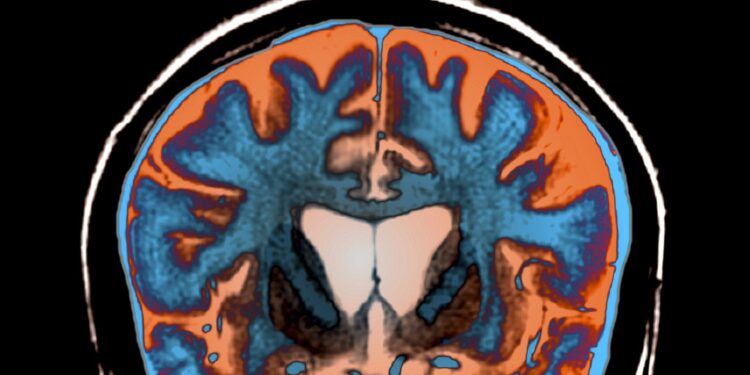

Le traitement proposé par uniQure s’appuie sur une intervention neurochirurgicale guidée par IRM. Les praticiens injectent directement dans le noyau caudé et le putamen (régions cérébrales fortement touchées) un virus modifié transportant un micro-ARN. Ce fragment génétique a pour mission de diminuer la fabrication de la huntingtine défectueuse.